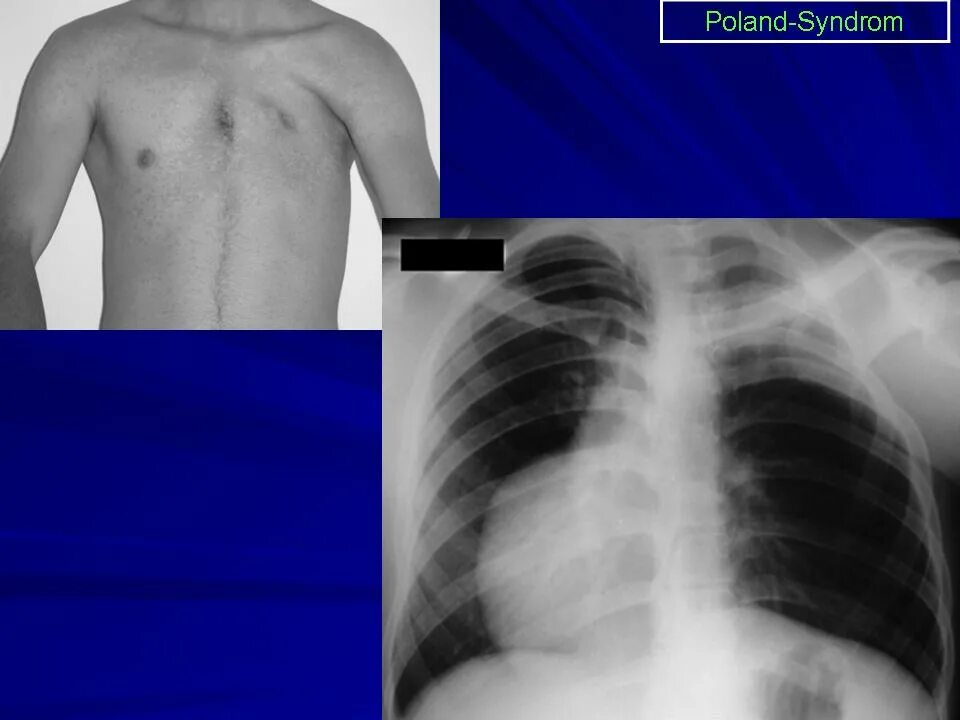

Мышечный дефект